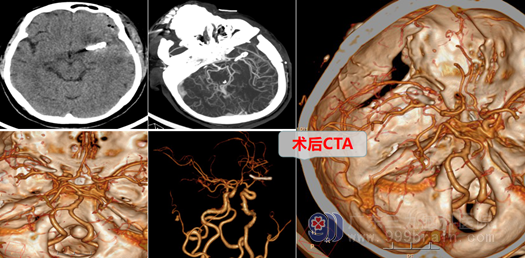

今年46岁的熊阿姨一周前无明显诱因出现头痛,无意识障碍及恶心呕吐,在当地医院就诊检查提示蛛网膜下腔出血,CT检查示“左侧大脑中动脉M1段动脉瘤”,熊阿姨当时听到自己得了“脑动脉瘤”焦急万分,情绪异常低落,家人因对动脉瘤不是很了解,以为熊阿姨得的是不治之症,四处打听寻求就医,在亲朋好友的帮忙下,熊阿姨在家人陪同下于2022年9月1日慕名来到广东三九脑科医院外十科就诊,接诊的是外十科的樊医生,在樊医生的安排下熊阿姨顺利住进了外十科,入院后樊医生马上安排做相关的检查,我院的CTA结果显示:“左侧大脑中动脉动脉瘤”,樊医生详细给熊阿姨一家解释了病情,好在熊阿姨当时动脉瘤还不是大破裂,只是有点开始渗血,这时更有完全破裂的危险,动脉瘤一旦真破裂出血将危及生命且及时获救术后预后也可能不是很好,熊阿姨一家也很庆幸能及时发现,不过要成功夹闭动脉瘤也存在风险,此时确实是:如履薄冰、如临深渊。樊医生和熊阿姨的家人详细谈话后,其家人也表示能理解。

外十科团队在欧阳辉主任的带领下,为熊阿姨设计了精细的手术方案,9月5日由欧阳教授主刀为熊阿姨在全麻下进行了左侧大脑中动脉瘤颈夹闭术,术中显微镜下放大,医生小心翼翼,就像“拆弹”一样,找到动脉瘤颈,精确夹闭之,并载瘤动脉保持通畅。术程很顺利,术后给与止血、控制血压、预防癫痫、抗血管痉挛等对症处理,术后第一天,熊阿姨神志清醒,四肢活动都很正常,也没有出现其他并发症,熊阿姨的家人看到她一天天的好转惊喜万分,也为现在的医学技术所惊叹,原以为是不治之症,没想到术后能恢复得这么好,熊阿姨术后经过一周多的治疗就顺利办理出院了,出院时熊阿姨的心情也非常好,感觉获得了第二次生命。